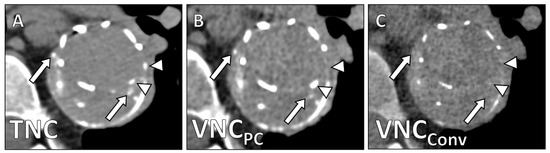

| TNC | VNCPC | VNCConv | Friedman X2 | p | Subgroup Analysis | p | |

|---|---|---|---|---|---|---|---|

| CT values/HU | 44.4 ± 15.5 | 39.1 ± 15.8 | 33.2 ± 15.9 | 19.6 | 0.006 | TNC/VNCPC TNC/VNCConv VNCPC/VNCConv | 0.013 <0.001 <0.001 |

| Noise/HU | 14.9 ± 7.1 | 16.7 ± 7.1 | 18.6 ± 5.3 | 22.8 | 0.003 | TNC/VNCPC TNC/VNCConv VNCPC/VNCConv | <0.001 <0.001 0.021 |

| SNR | 3.3 ± 1.6 | 2.5 ± 1.3 | 1.9 ± 0.9 | 25.0 | <0.001 | TNC/VNCConv TNC/VNCConv VNCPC/VNCConv | <0.001 <0.001 <0.001 |

| Image Quality | 4.2 ± 0.9 | 0.68 (0.44–0.78) | 2.5 ± 0.6 | 0.62 (0.43–0.77) | <0.001 |

| Calcium Subtraction | 4.6 ± 0.5 | 0.75 (0.66–0.82) | 3.0 ± 0.6 | 0.58 (0.40–0.71) | <0.001 |

| Stent Subtraction | 4.7 ± 0.7 | 0.72 (0.58–0.81) | 3.8 ± 1.2 | 0.62 (0.49–0.77) | 0.003 |

| Contrast Subtraction Aorta | 5.0 ± 0.0 | 1.0 (1.0–1.0) | 5.0 ± 0.0 | 1.0 (1.0–1.0) | 1 |

| Contrast Subtraction Total | 4.3 ± 0.8 | 0.86 (0.71–0.95) | 4.0 ± 1.1 | 0.79 (0.66–0.89) | 0.091 |